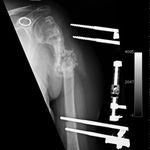

Some time in late May 2010, she presented with movement of the fracture site and was noted that the central area of healing had broken down and was thought that she had a deep infection. She was taken back to theater in mid June 2010 when operation showed that there was no pus. Multiple samples of the fracture site were taken and an external fixator applied with compression of the fragments. Following that, the cultures taken from the wounds showed no growth and no organisms and a biopsy showed no sign of any malignancy or abnormal cells. The fixator became loose and eventually had to be removed. This was done in July 2010 and she was discovered to be going onto a hypertrophic nonunion. Low dose ultrasound treatment of the fracture site was tried to help stimulate healing over the course of a few months but the non union persisted.

She was advised of the need to do some sort of stabilization which is necessary since the use of low-dose ultrasound has not helped in the healing process. She was unwilling to have any further operative intervention and sought further options. Eventually, she agreed to a fourth procedure of intra-medullary nail stabilization of the fracture and had this carried out in April 2011. An intramedullary nail was inserted in an antegrade manner and she has since gone on to heal the fracture site completely and has regained most of the function of the upper limb with no pain.